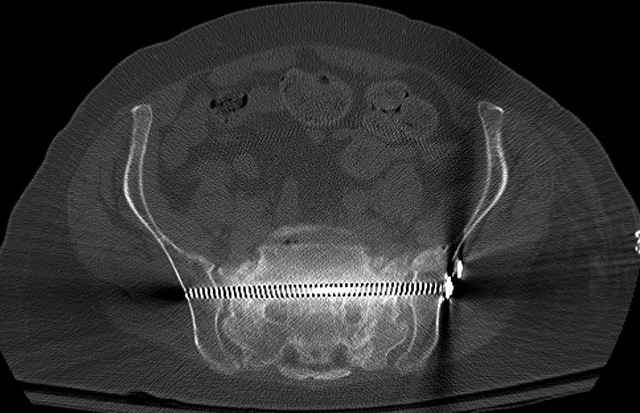

Here are a recent patient’s example slides...

54 yo Female Fell c/o Pain

Pelvic CT Scan - 3 Months After Fall

Sacral Injuries

Ramus Fractures

Percutaneous Fixation

(B) Ramus-Retrograde

2 TransIliac-TransSacral

Upper Segment